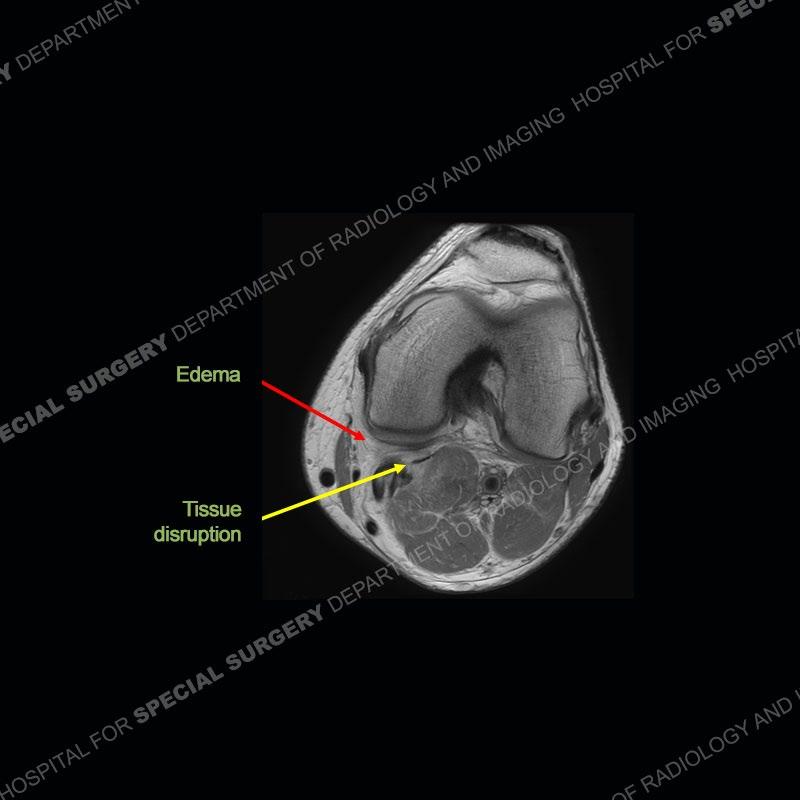

Diagnosis: Partial Disruption Medial Head Gastrocnemius (MHG)

The findings were kept purposefully vague as identifying the structures early on takes away a lot of the diagnosis. An uncommon entity and one of which we do not see a lot. Enthesopathic changes and tendinosis are seen as are distal MHG injuries, but proximal tears are rarely present. This case highlights a number of points. One, it almost always comes down to anatomy. Perhaps not a structure we normally spend too much time on, except save for diagnosing a Baker’s cyst, but knowing where this structure and all structures exist in all three planes is imperative. Second, when you think you are making a “call” or finding that you have never made before, step back and think is this just the abnormal presentation of a common pathology. That situation arises much more frequently. Third, if you look at it once, twice, and probably a third time and are confident in your odd or very rare diagnosis, stick to your guns. Especially, when it comes down to anatomic structures, the proof will be in the images.

Fourth, use all imaging planes and different pulse sequences to make your diagnosis. The edema highlighted in this case can be seen as the obscuration of fat on the PD images but is much easier to perceive as the high signal on the IR pulse sequences. The actual disruption of the MHG myotendinous junction is only able to be seen on the axial images. On the sagittal and coronal images, we get a sense something is wrong but hard to be exact. Lastly, when you look at a study and something just seems off (as I would say the sagittal and coronal images do with that dark band of tissue posteriorly), listen to yourself and go through the study slowly and meticulously. Most of the time you will find you were right, and something indeed is present.